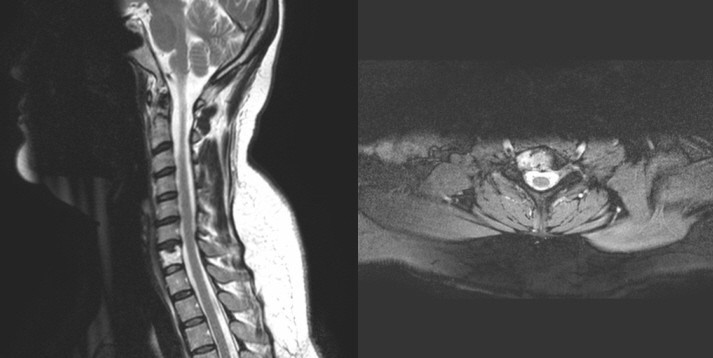

Mri Cervical Spine Sagittal Anatomy

A 24-year-old Woman With Neck Pain

Figure 1 Sagittal T2w Mri Of The Cervical Spine Shows A Chiari I Malformation Thick White